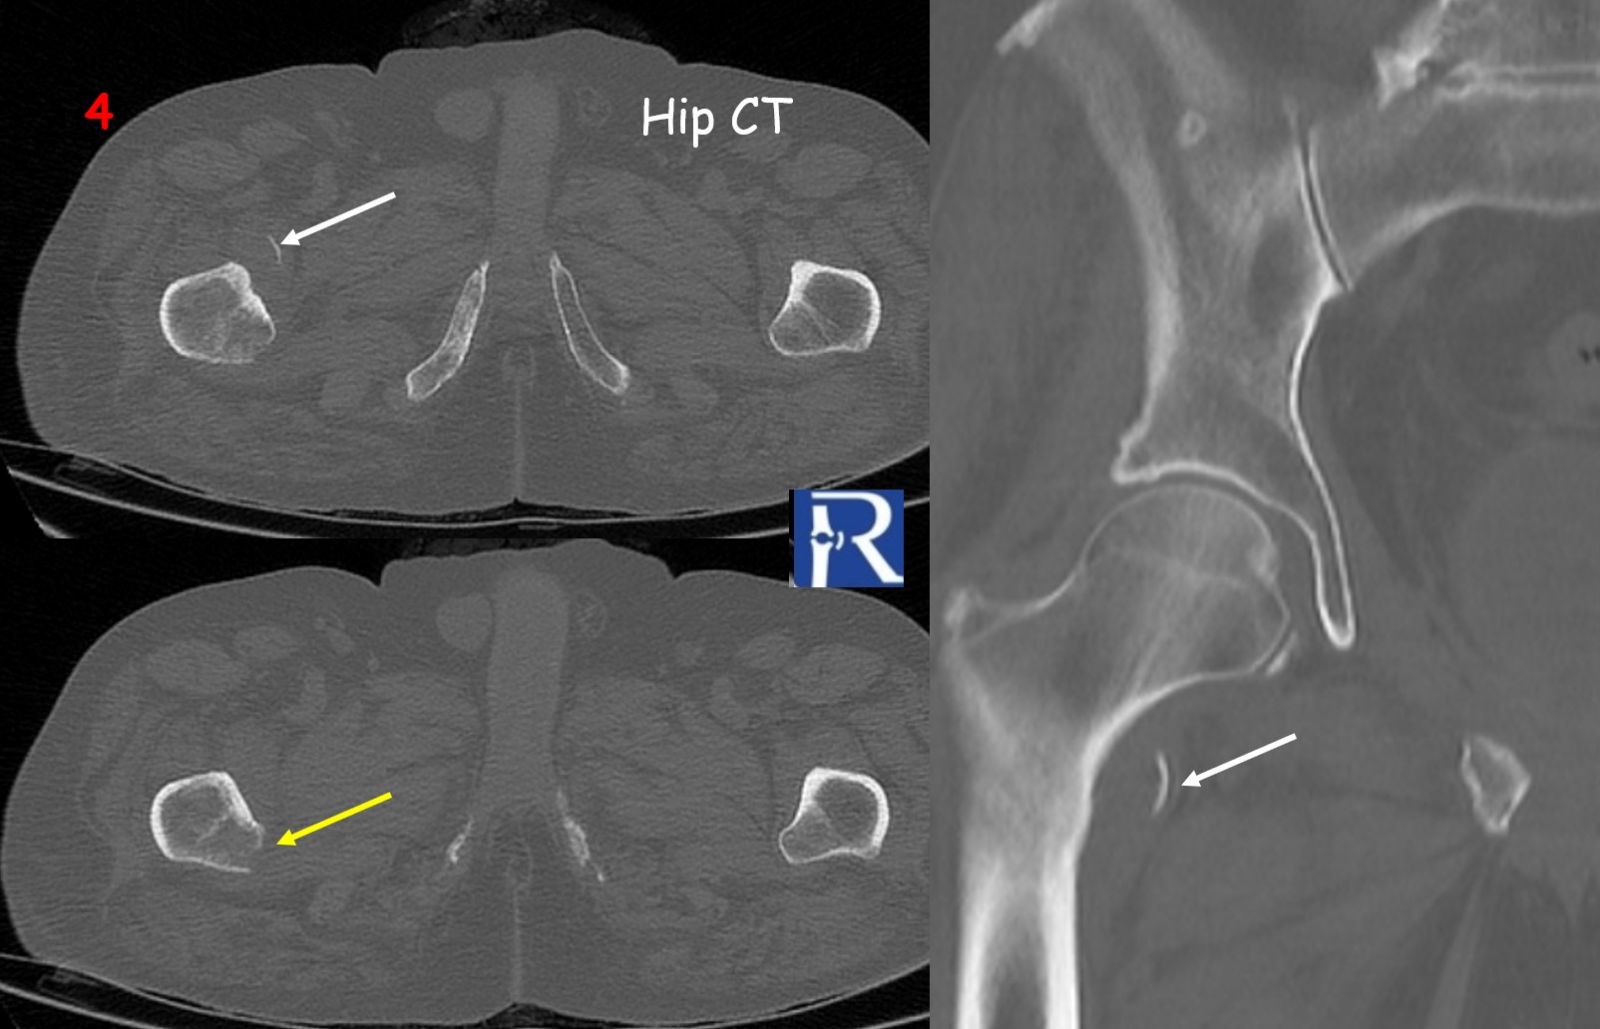

CT imaging (Figures 3–4) confirmed the avulsion fracture and better delineated the underlying osteolytic lesion at the lesser trochanter, consistent with cortical destruction.

⚪ White arrows → Avulsed bone fragment

???? Yellow arrows → Cortical defect at the lesser trochanter